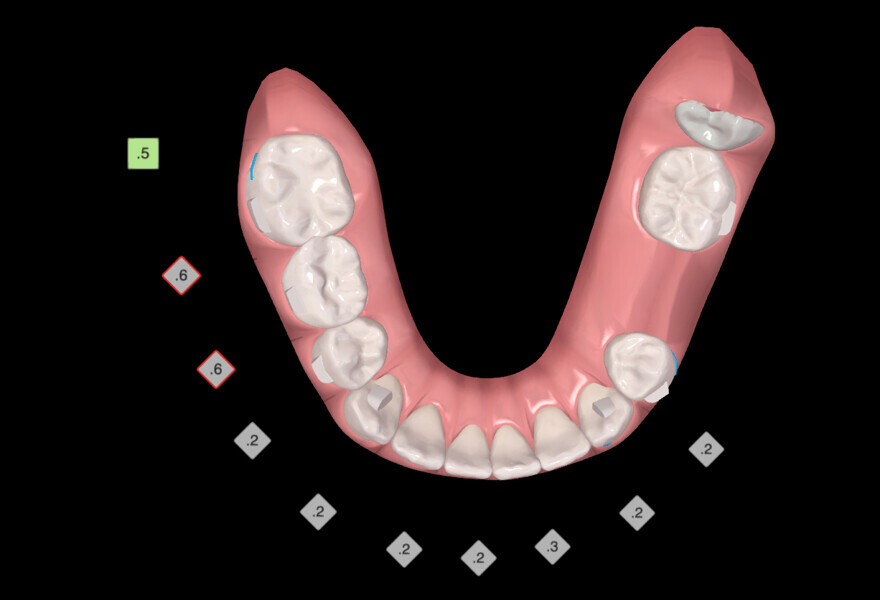

The digital treatment plan (ClinCheck) provided 18 aligners in each arch. The treatment objectives were focused on aligning and levelling the mandibular arch without excessively proclining the mandibular incisors, in order to control the Class III skeletal malocclusion by means of interproximal reduction and slicing of tooth #85. In the maxillary arch, the treatment plan focused on space creation for tooth #13 by distal rotation of the maxillary right molar and mesialisation of the maxillary right lateral incisor simultaneously to centre the midlines. Class II elastics were planned to control distal movement on the right side, and triangular elastics on the high canine were planned on the left side with button cutouts for the aligners. Lateral and posterior maxillary torque were planned to be close to 0° to achieve wider arch design and ideal intercuspation. No digital over-engineering was planned in the set-up, and lingual attachments according to personal preference were placed in the maxillary arch for aesthetic and biomechanical reasons (Figs. 15–19). Eruption compensation for tooth #13 was employed. Because of the age of the patient, the aligners were changed every seven days over the treatment period of less than five months.

At the end of the first stage of aligner treatment (Figs. 20–24), the auxiliary phase began with the bonding of two MTAs on the maxillary right premolars. A 0.016-in Australian archwire, shaped into a cantilever configuration, was then inserted into the MTAs, and a cutout was created on the final aligner. To prevent rotation, the archwire was cinched distal to tooth #15 and the cinch covered with composite.

At the same time, the impacted canine was exposed by laser, a button was bonded on to it and the cantilever was connected to the button using an elastomeric thread. The final aligner was used for space maintenance while the cantilever was reactivated until the canine had erupted (Figs. 25–27). After complete eruption, further MTAs were bonded on the canine and on the lateral incisor, and a 0.014 in. NiTi archwire was used to finalise the eruption (Figs. 28–30). Only at the end of the forced eruption phase did the further aligner stage take place, aimed at achieving an ideal Class I relationship on the right by maxillary right mesialisation using Class III elastics and 27 maxillary aligners and 13 mandibular aligners (Figs. 31–33).